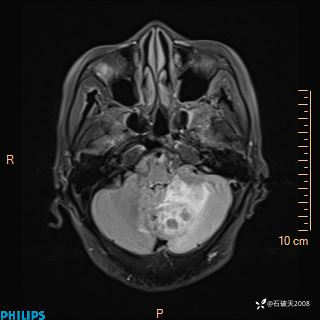

女 86岁 主 诉:乏力1月

现病史:患者1月前活动出现双下肢乏力,无头晕、头痛、恶心、呕吐、肢体活动不利,休息后缓解,间断断发作,症状进行性加重,在家口服药物治疗(具体不详),效差,为进一步诊治,来我院,门诊按“乏力”收住我科,患者自发病以来,神志清,精神稍差,饮食睡眠欠佳,大小便正常,体重未见明显改变。

T2

T1